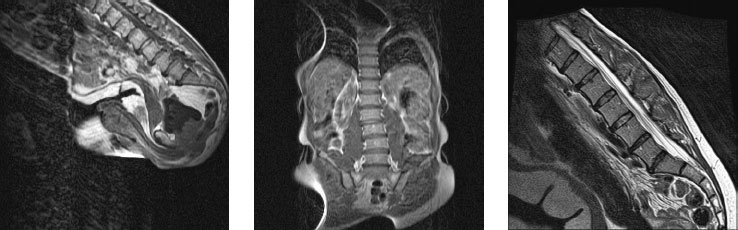

Иллюстрация к книге — Йога при остеопорозе [_27.jpg]

Рисунок 24. Несмотря на разные школы, разные десятилетия, разные континенты, разный пол и разный по продолжительности опыт занятий йогой, здесь мы не видим значительных различий в положении поясничных позвонков.